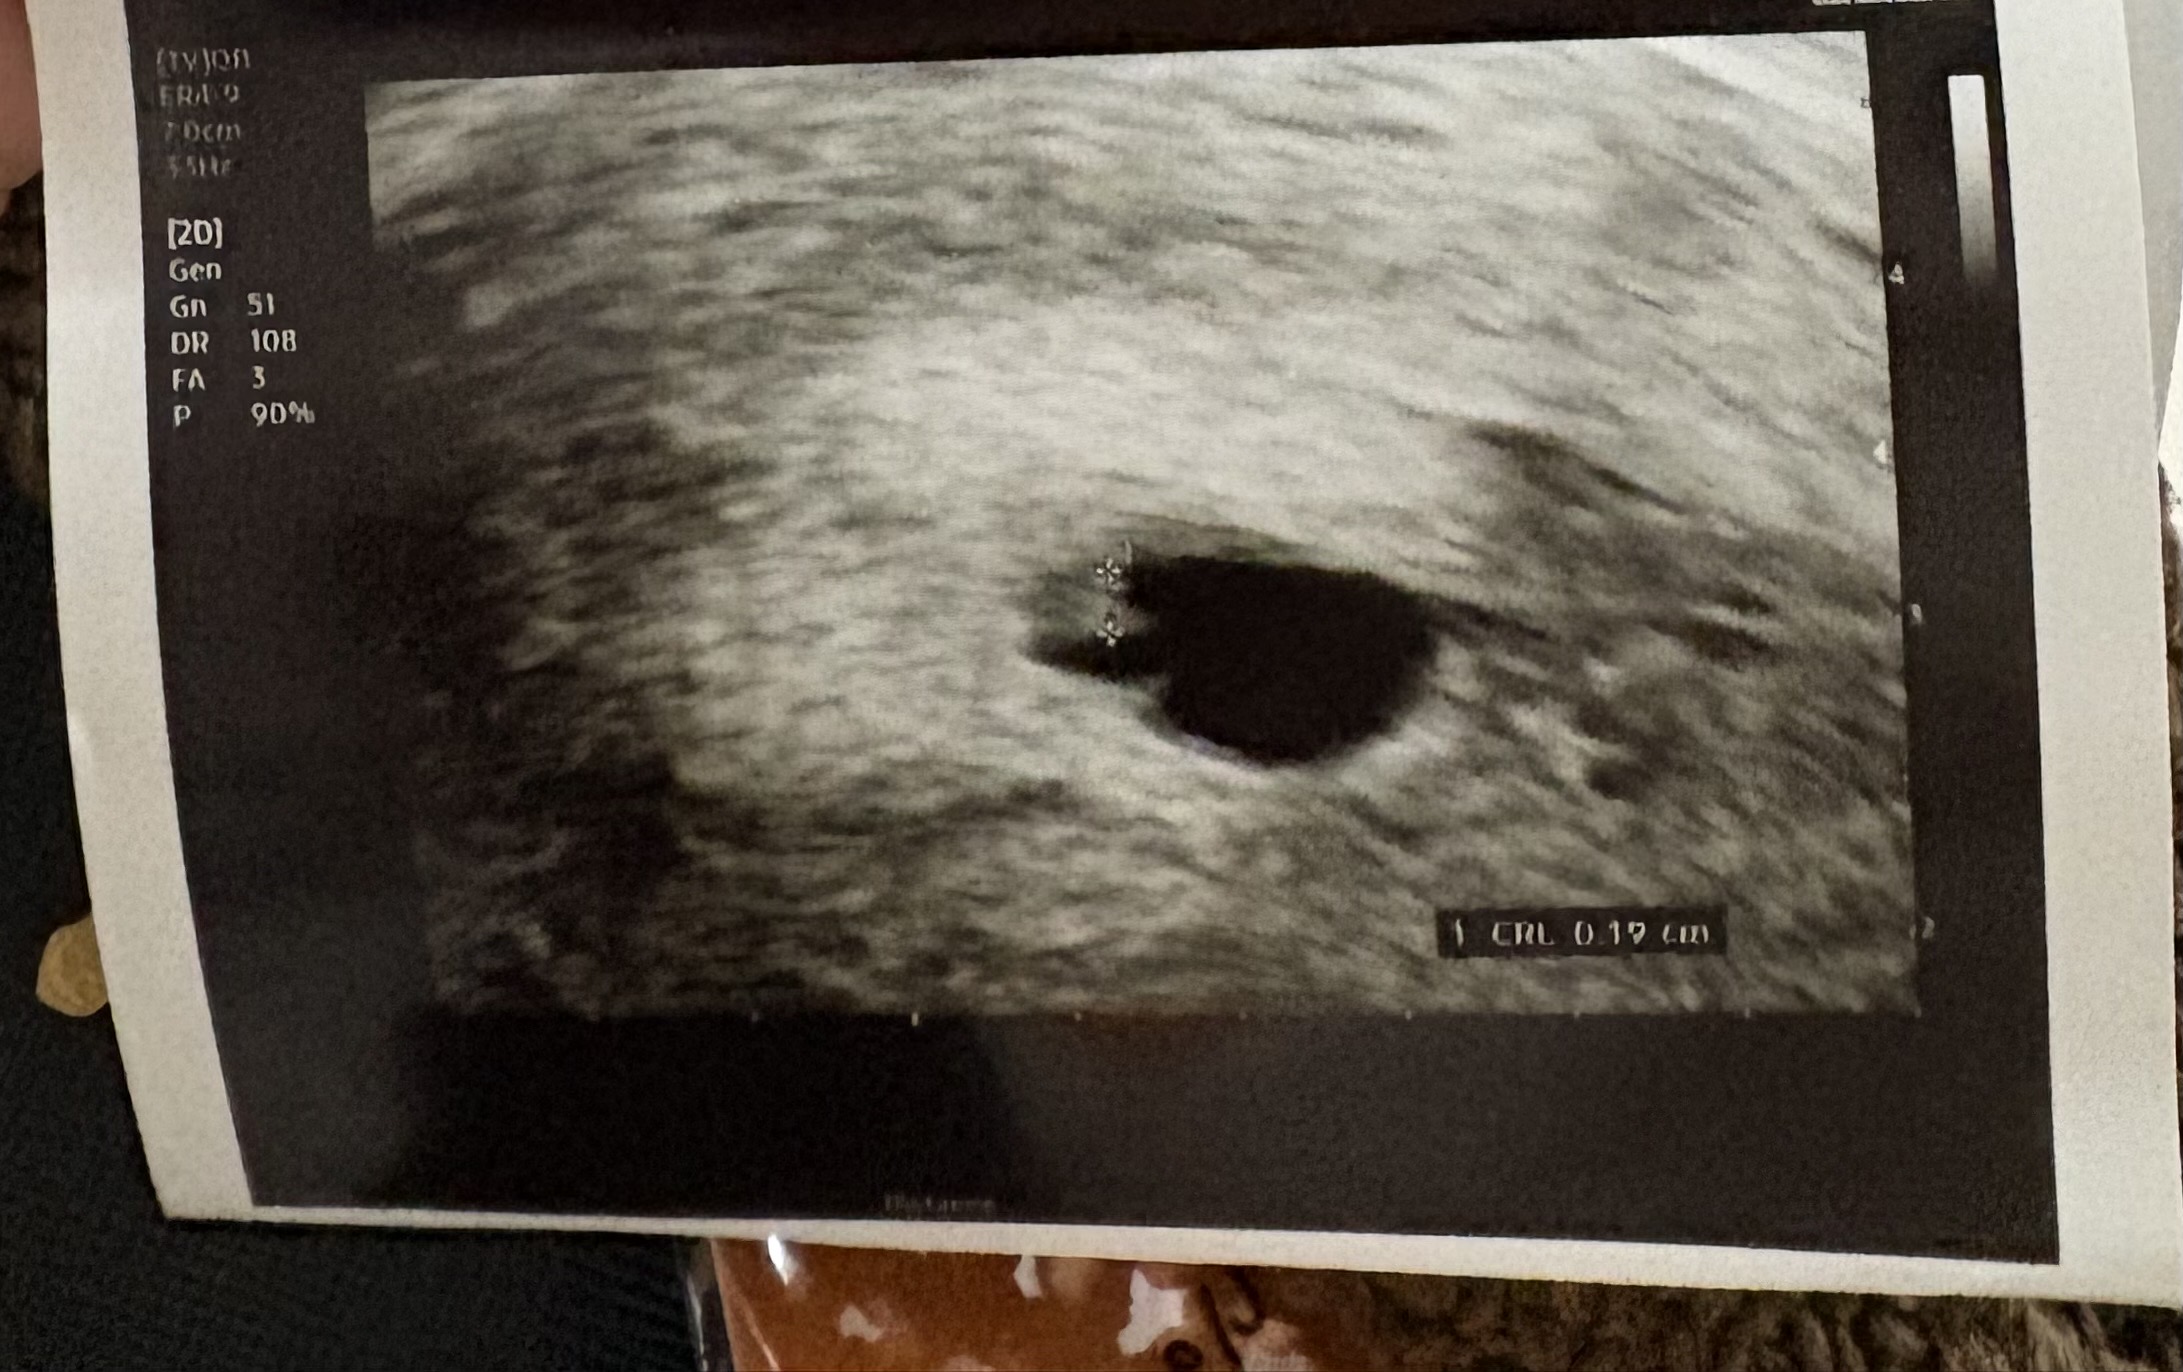

심장소리 듣고 왔구요 심장소리는 113 아기는 0.19 0.22 이렇게 되더라구요 다른 분들에비해서 작은것 같아서 불안합니다ㅠㅠ 아기도 그다지 뚜렷하지 않은 것 같고 .... 저같은 분들 있으셨나요